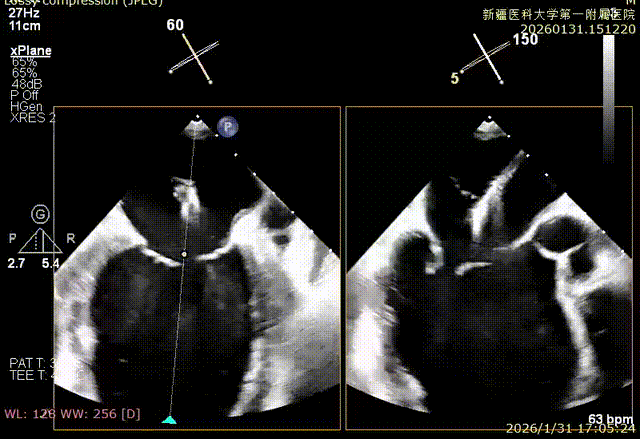

SGC进入左房

XTR初定位

XTR弹道测试

房间隔成功穿刺